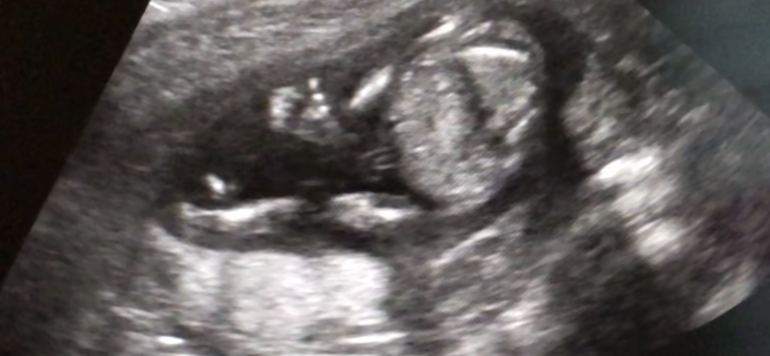

Мне кажется это мальчик. На втором фото видно писюнь, но это бугорок пока. Он вытянут вперед. Незнаю почему все говорят девлчка. Вам подтвердили пол?

По второму фото вижу кофейное зёрнышко, у нас так же в 16 недель было. Думаю что девочка

Девочка) а то, что вы возможно высмотрели на втором фото, скорее пуповина пежду ножек. Я платно все узи проходила, хоть никто не читал морали и прочее, в 16 недель сказали точно пол, далее только подтверждали